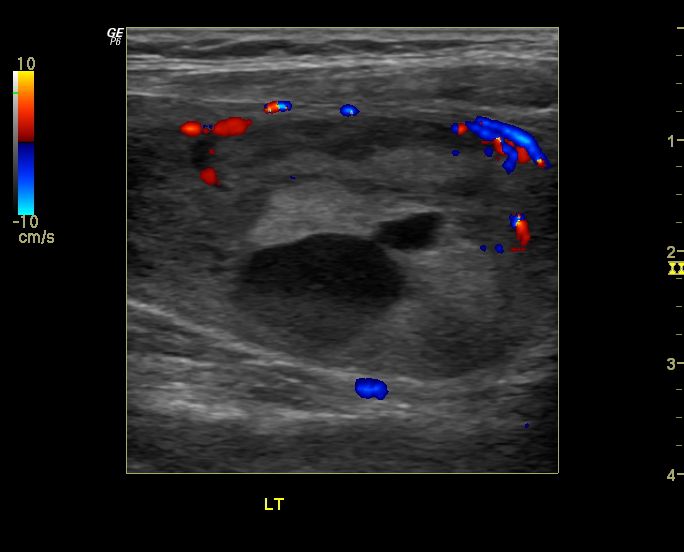

Ultrasound imaging Multiplecolloidnodulesthyroid Colloid Nodule Management Clinical history and examination, serum thyroid stimulating hormone (tsh) measurement, ultrasound and, if indicated,. A thyroid colloid cyst is a noncancerous nodule filled with thyroid hormone. There are four key components to thyroid nodule assessment: Learn how it is diagnosed with ultrasound, blood tests, and other methods, and what treatment. About 50% of nodules are solitary, with another 25% being. Colloid Nodule Management.

From ultrasound-images.blogspot.com